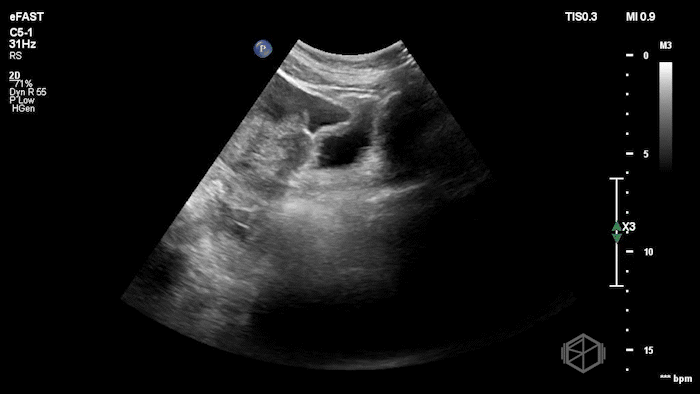

Drs. Ariz and Scavelli were caring for an approximately 40-year-old woman, G2P1, at approximately 8 weeks gestation, who presented to the ED with abdominal cramping. She was hypotensive on arrival, prompting the team to reach for the ultrasound immediately. They saw the following:

POCUS showed free fluid throughout the abdomen, including the RUQ, LUQ, and pelvis. The uterus was empty, and the final clip appears to show a complex left adnexal mass.

Diagnosis: Left ectopic pregnancy with hemoperitoneum